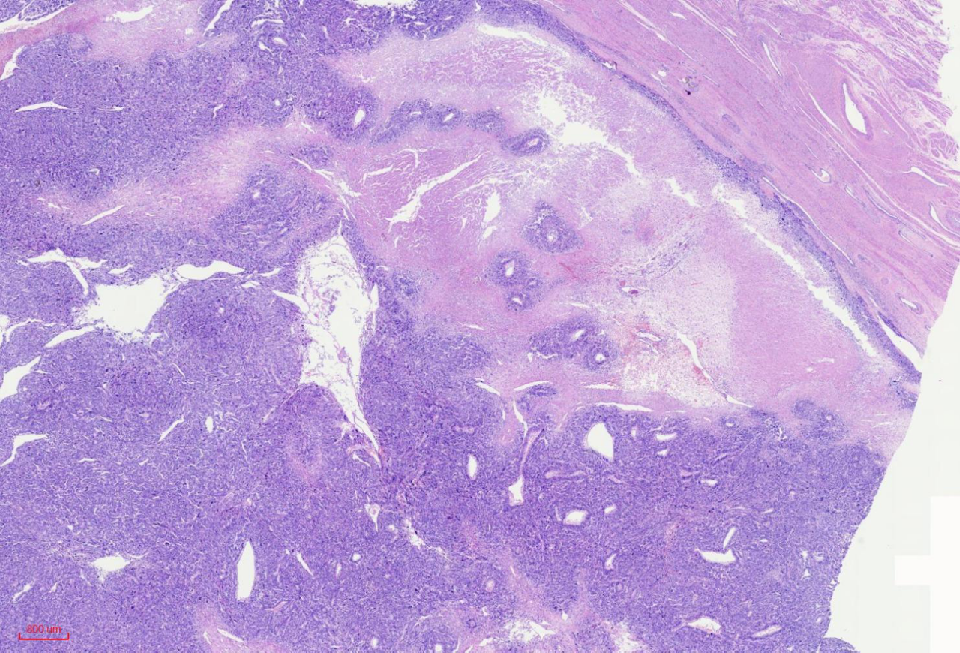

组织学改变

肿瘤与周围境界清楚

肿瘤细胞丰富

瘤细胞排列呈血管外皮瘤样

瘤细胞疏密相间

异型明显,可见核内包涵体,红核仁

未见凝固性坏死

核分裂象数2个/10HPF

肿瘤境界清楚

细胞丰富

鹿角样/血管外皮瘤样血管

肺水肿样水肿/疏密相间

细胞核奇异,嗜酸性胞质,有显著的嗜酸性核仁,核仁周围可见空晕,部分细胞呈横纹肌样

核分裂象少见

无凝固性坏死